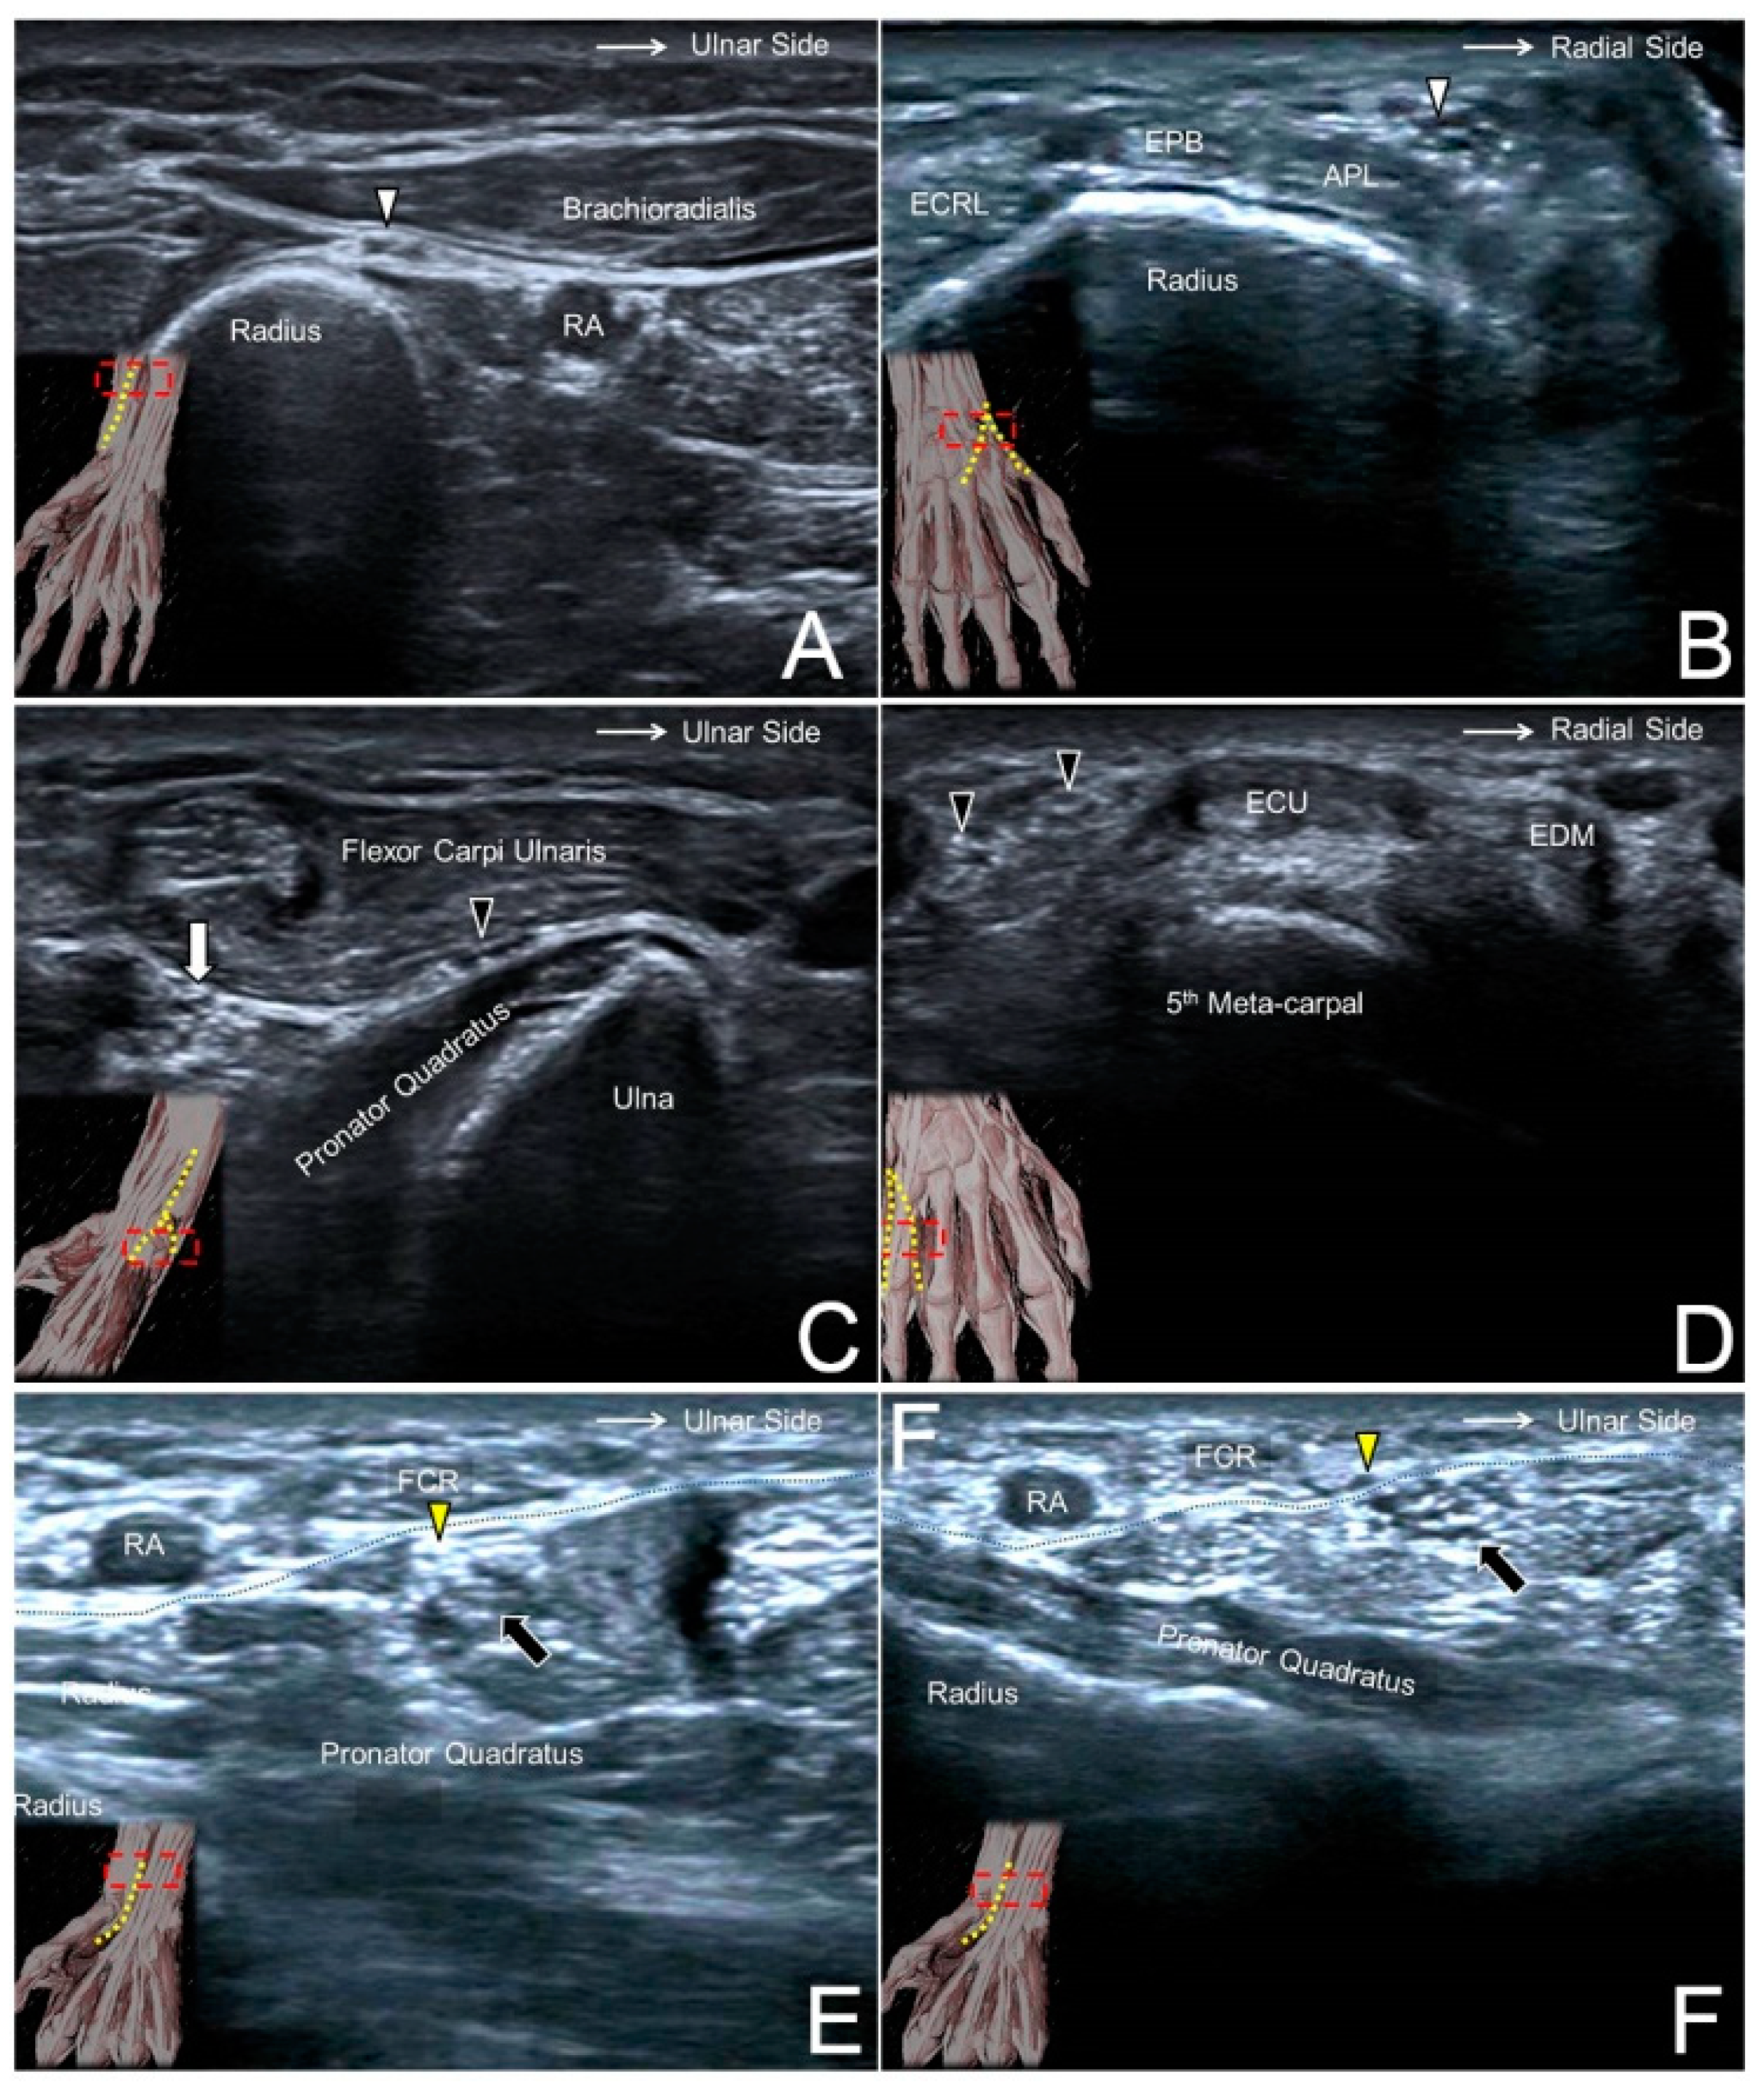

Figure 7. The superficial radial nerve (white arrowhead) at the level of the distal forearm (A) and the radial dorsal wrist (B). The dorsal ulnar cutaneous nerve (black arrowhead) at the level of the distal forearm (C) and the ulnar side of the dorsal wrist (D). The palmar branch of the median nerve (yellow arrowhead) at the level of the distal forearm (E) and emerging from the antebrachial fascia (black dashed line) (F). RA, radial artery; ECRL, extensor carpi radialis longus muscle; APL, abductor pollicis longus tendon; EPB, extensor pollicis brevis tendon; white arrow, ulnar nerve; black arrow, median nerve.

7.2. Scanning Technique

The transducer is placed at the lateral side of the elbow crease to locate the radial nerve interposed between the brachioradialis and brachialis muscles. Moving the transducer more distally, the SBRN is seen branching from the medial aspect of the radial nerve and descending underneath the brachioradialis muscle (Figure 7A). More caudally, the nerve initially courses next to the radial artery and then leaves it in the distal third of the forearm. The SBRN later pierces the antebrachial fascia between the extensor carpi radialis longus and brachioradialis tendons and runs towards the dorsal radial aspect of the wrist/hand (Figure 7B, Supplementary Video S6) [21].

8.2. Scanning Technique

The transducer is placed on the distal third of the ventral forearm to locate the flexor carpi ulnaris muscle, underneath which lies the ulnar nerve. Moving the transducer more distally, the DCBUN is seen branching from the medial aspect of the ulnar nerve (Figure 7C). It then circles around the distal ulna, courses above the extensor carpi ulnaris tendon, runs towards the ulnar side of the dorsal hand, and gives off two or three terminal branches (Figure 7D, Supplementary Video S7) [24].

9.2. Scanning Technique

The transducer is placed on the distal forearm to visualize the median nerve interposed between the flexor digitorum superficialis and profundus muscles. Moving the transducer more distally, these muscles become tendons and the median nerve transits superficially to course underneath the antebrachial fascia. The PCMN emerges from the radial aspect of the median nerve and circles around the upper border of the median nerve to reach the antebrachial fascia (Figure 7E). The PCMN later pierces this fascia and runs at the ulnar aspect of the flexor carpi radialis tendon (Figure 7F, Supplementary Video S8) [27].